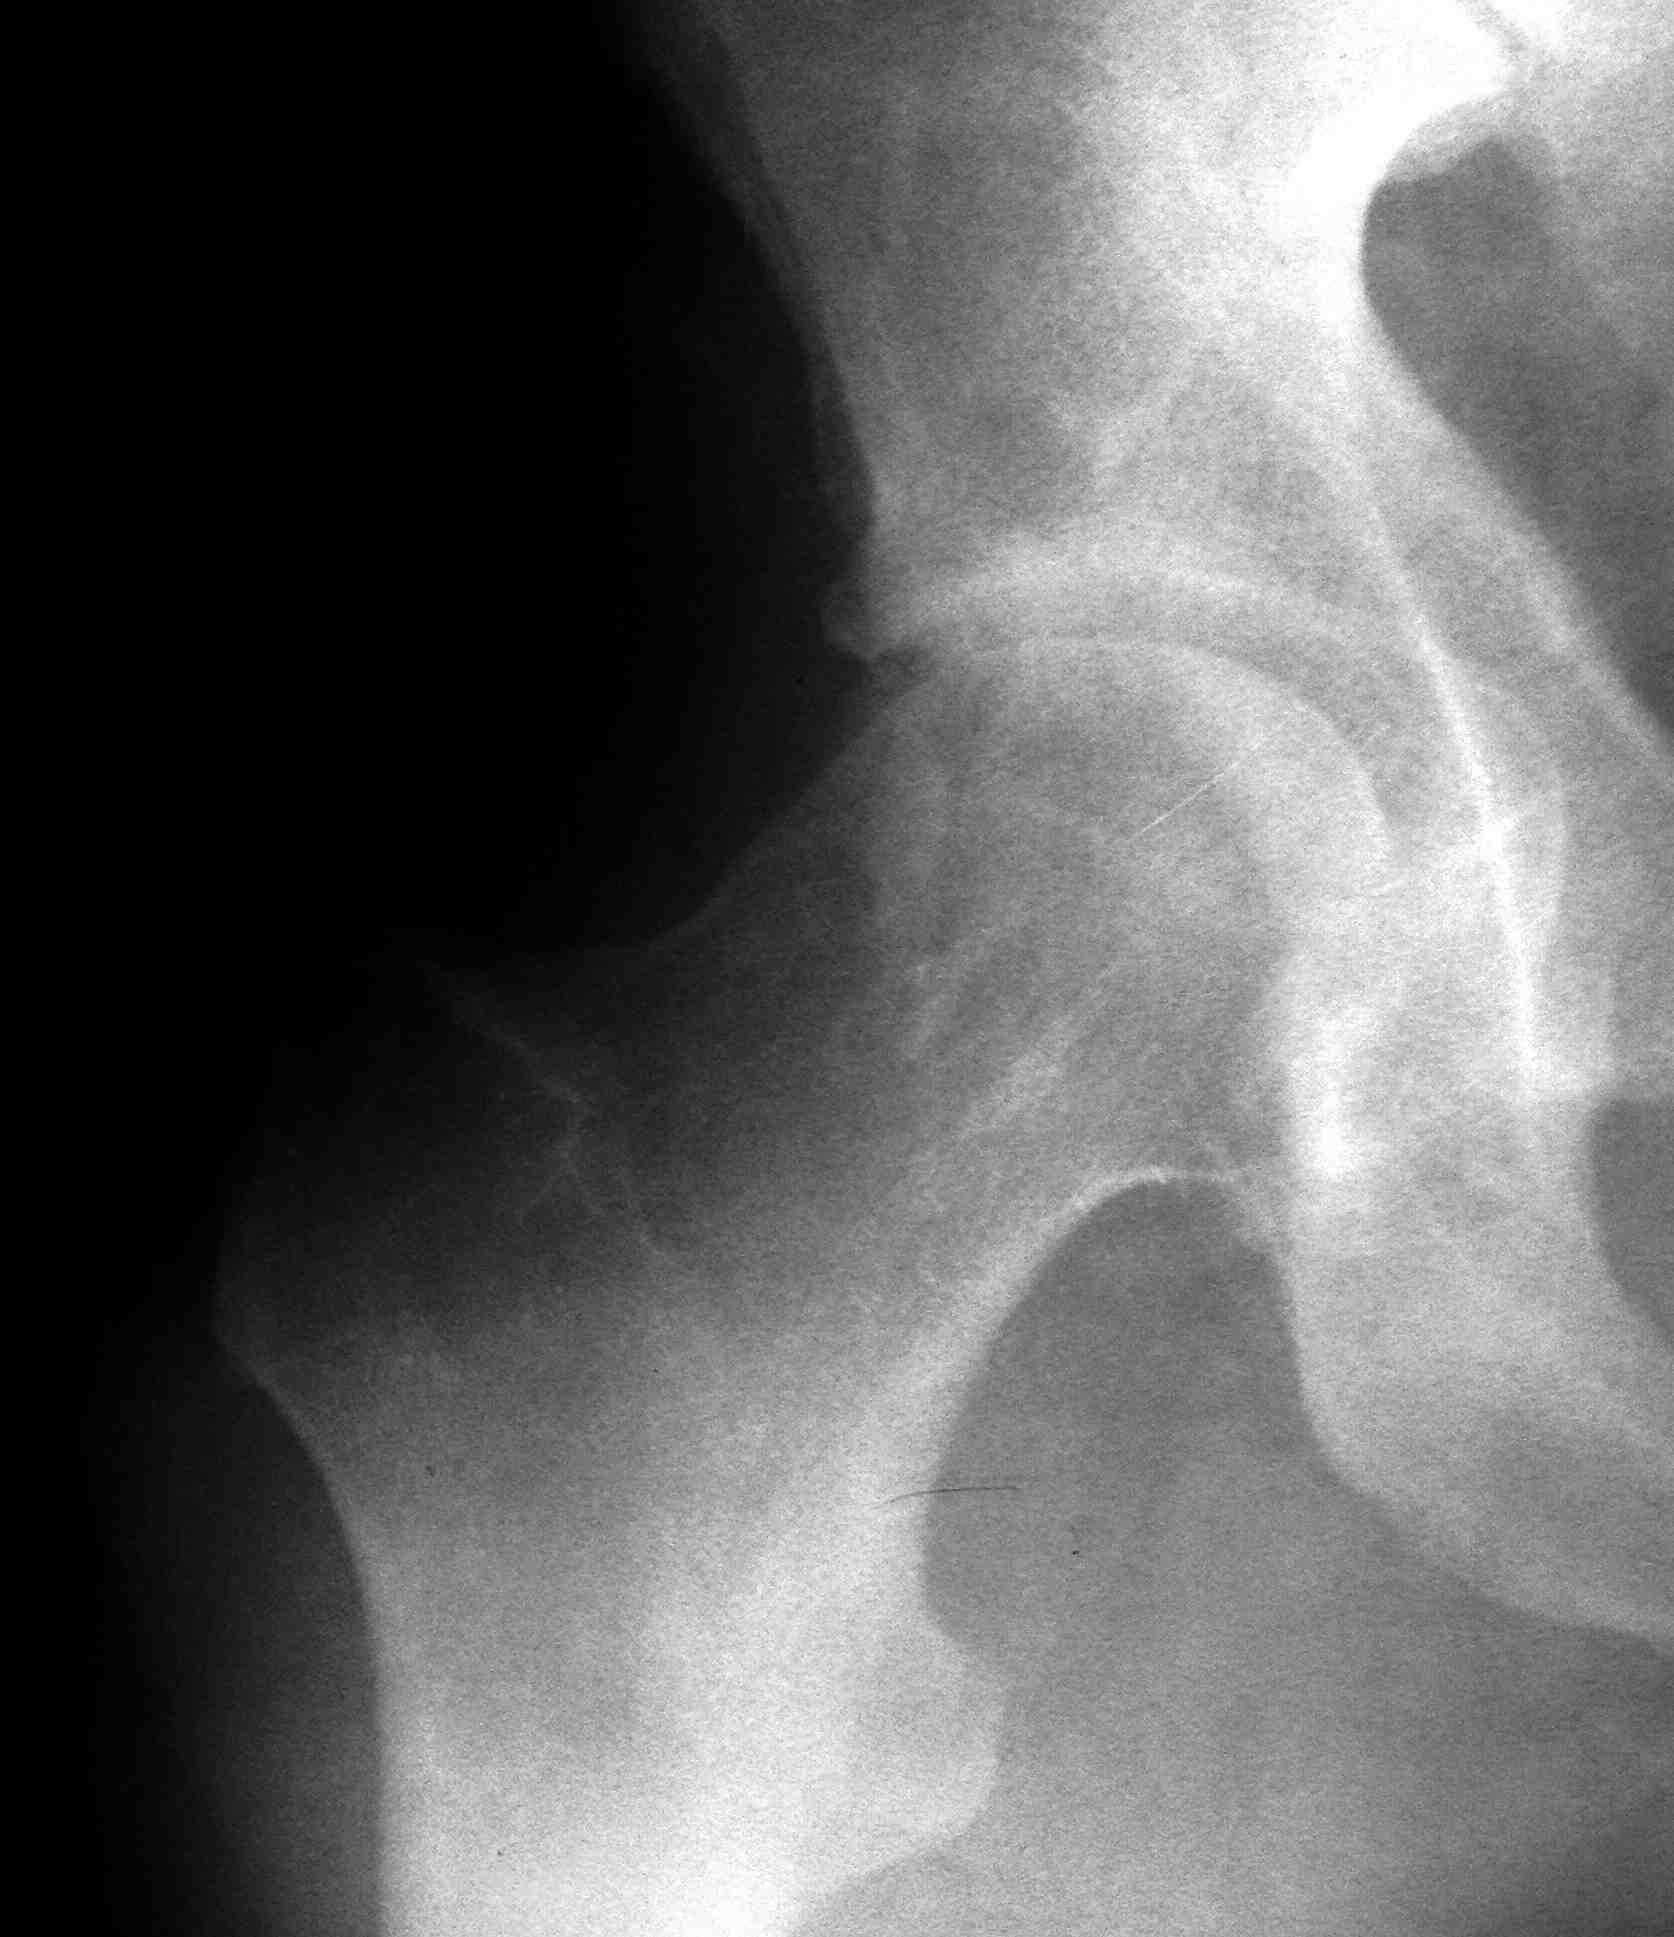

[Ortho] перелом проксимальной тибии + вывих бедра

Высокоэнергетическая травма около недели назад, мужчина 39 лет

По месту поступления вывих бедра вправлен, ПХО раны открытого перелома

б/б кости, скелетное вытяжение. В настоящее время рана заживает неплохо,

небольшое количество серозно-геморрагического отделяемого, состояние

мягких тканей неплохое. Планируем остеосинтез плато из 2-х доступов по

заживлению раны.

2 часть задней стенки в суставе, такое впечатление, что она больше ямки

и подвывихивает сустав или это ошибочное впечатление?

3. насколько целесообразно искать этот фрагмент во впадине и пытаться

засинтезировать задний край при наличии довольно выраженного FAI?

Попробовать при вывихе полечить и то и другое (практического опыта

лечения FAI нет, шаблонов для головки тоже, артроскопия т/б недоступна)?